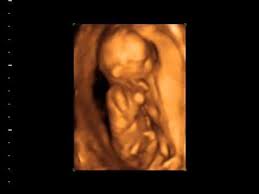

Your 4d Baby Ultrasound Studio. Jacksonvilles premier 2D 3D 4D and 5D ultrasound studio. We specialise in elective 2D 3D4D ultrasound providing a positive bonding experience for mums-to-be and their families.

Located in Murfreesboro TN we establish a connection between you and your baby long before they enter the world. BabyTime 3D4D Ultrasound Studio Inc. Jacksonvilles premier 2D 3D 4D and 5D ultrasound studio.

Is a full service elective imaging studio happily serving the Middle Tennessee area.

Keepsake recording of your babys heartbeat add 10. Jacksonvilles premier 2D 3D 4D and 5D ultrasound studio. How blessed am I to share this with families every day Michael Benito yawning on a lazy Friday afternoon. I f you are looking for a prenatal ultrasound and the best non medical 3D 4D ultrasound Premium imaging facility in Miami.